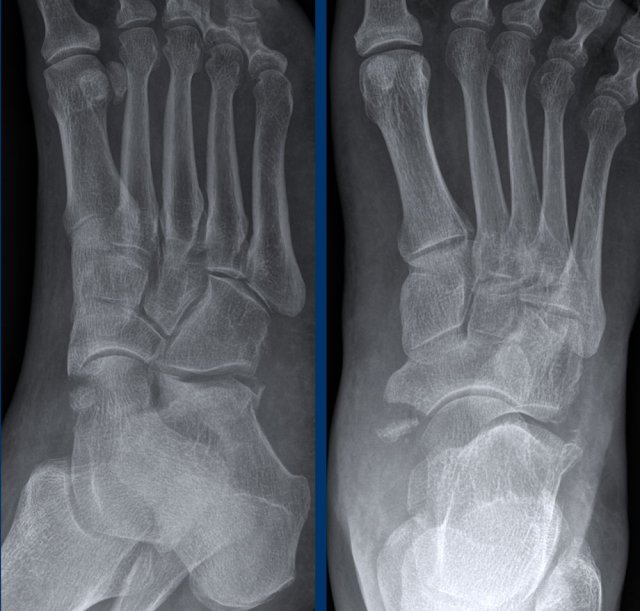

case 3 - ankle distortion

What are the findings?

What is the stage of this injury?